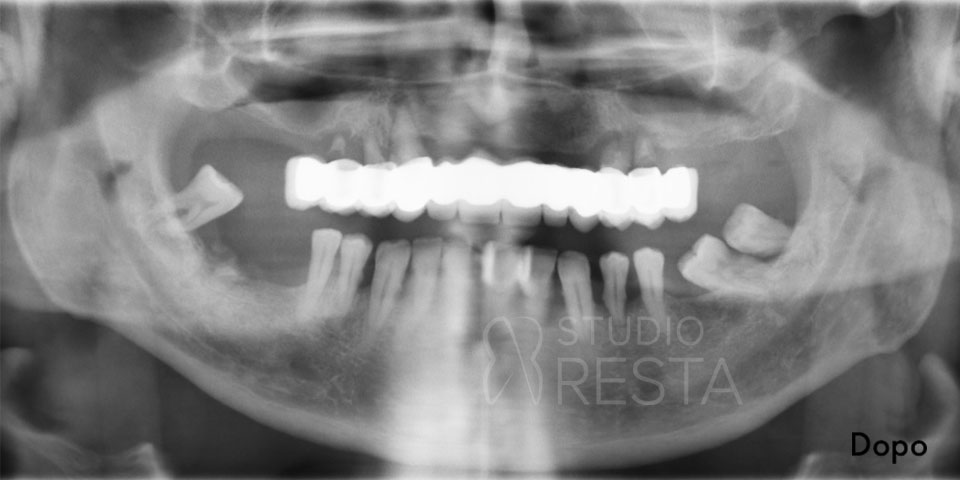

Prima di confermare la fattibilità di un impianto dentale All on Four, eseguiamo uno studio diagnostico approfondito. Presso il nostro studio, in un’unica seduta, realizziamo sia l’ortopantomografia digitale (radiografia panoramica) sia una TAC Cone Beam 3D a basse dosi, per valutare con precisione lo spessore e l’altezza dell’osso nelle varie zone dell’arcata. Questi esami ci permettono di pianificare l’intervento in dettaglio. In base alle immagini 3D, il dentista implantologo studierà la posizione ideale per ciascun impianto, evitando strutture delicate e massimizzando la stabilità.

- Esami diagnostici iniziali: prima dell’intervento effettuiamo in studio tutti gli esami radiografici necessari. Oltre alla classica radiografia panoramica (OPT), realizziamo una TAC Cone Beam 3D per studiare tridimensionalmente l’osso residuo. Questi esami guidano la pianificazione e garantiscono che l’intervento sia sicuro e senza sorprese.

- Controllo radiografico finale: a completamento dell’intervento, eseguiamo una radiografia di controllo (OPT) per verificare l’esatto posizionamento dei quattro impianti. Spesso si noterà che i due impianti posteriori sono inclinati verso la parte posteriore dell’arcata (tilted implants), confermando il caratteristico assetto “a V rovesciata” dell’All on 4.